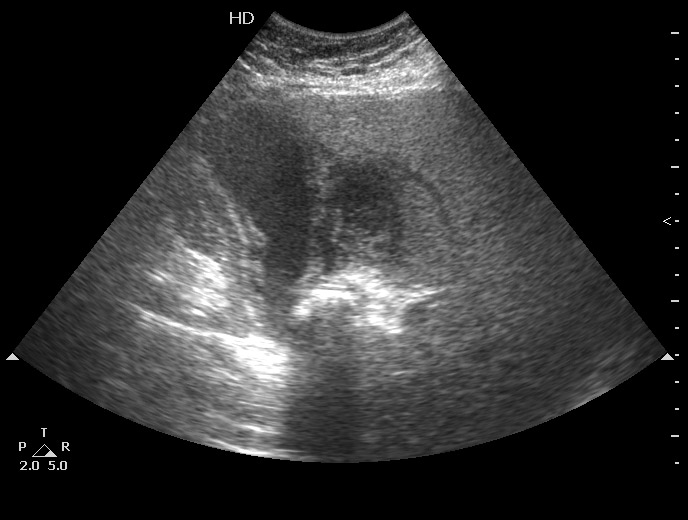

Заключение УЗИ: Диффузная форма рака желчного пузыря.

УЗИ - о.деструктивный холецистит

ЖКБ:конкремент в шейке ЖП, стенка пузыря утолщена, неравномерно эхогенна с двойным контуром и на всем протяжении не прослеживается- Эмпиема ЖП - возможно, острый гангренозный холецистит На снимке вокруг ЖП определяется гипоэхогенное образование без четких границ- перфорированный ЖП (гнойный перихолецистит ?) Только почему без температуры???

Вопрос "почему без температуры" волновал и хирургов, пациентку прооперировали через 2,5 недели после поступления, полностью подтвердив Ваше заключение.

Острый калькулезный обструктивный холецистит, эмпиема желчного пузыря, перфорация, околопузырный абсцесс.